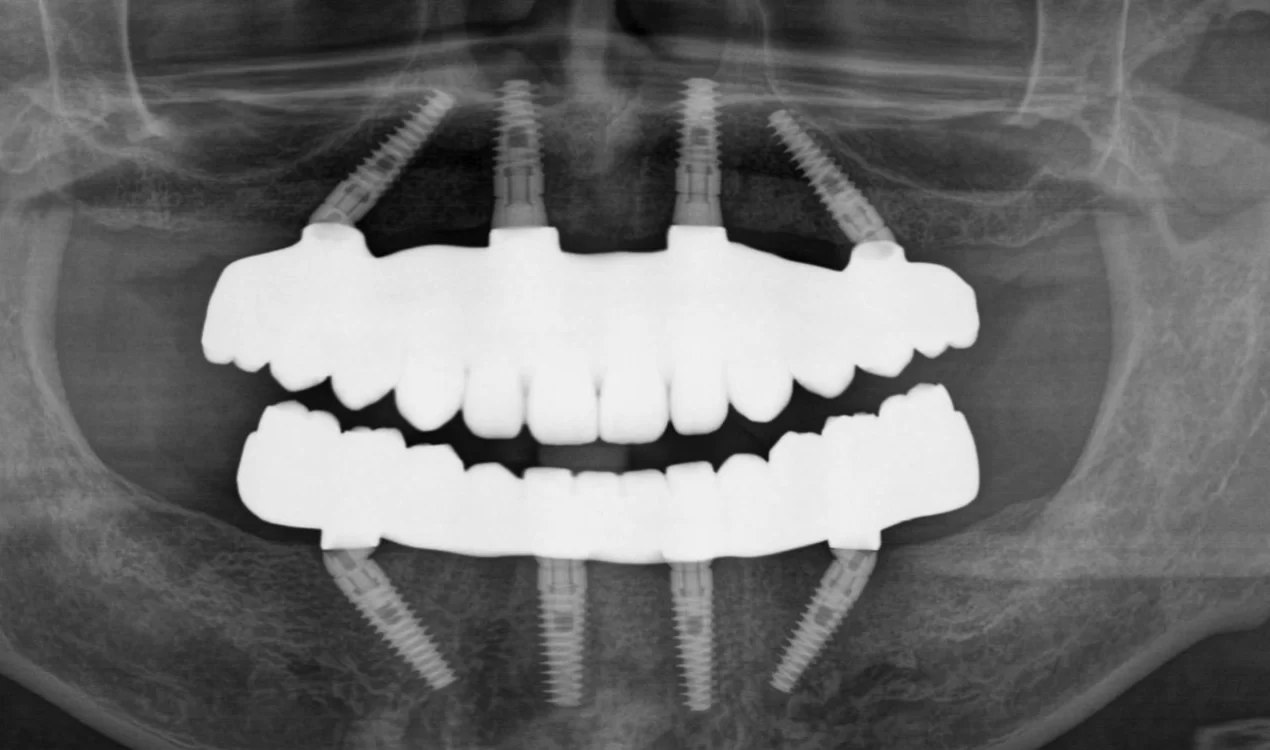

術前

内容 :上下顎オールオン4ザイゴマ0

費用 :4,365,900円

※モニター価格

期間 :半年

リスク:出血・腫れ・痺れ・痛み